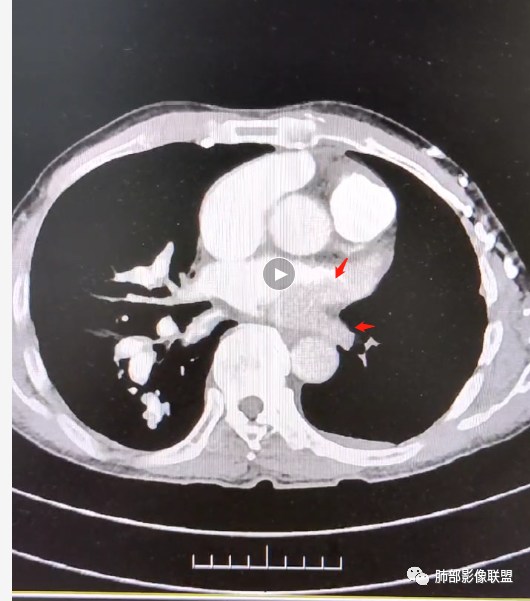

2.右肺广泛密度增高、腺泡结节样磨玻璃影,血管影明显扩张,小叶间隔增厚。

4.左肺相对广泛低密度、血管纤细(显著)。

6.心脏影增大,右房室增大为主。(增强:左心房及肺静脉入口见充盈缺损)

7.肺动脉主干扩张,左侧肺动脉主干见混杂密度影,上下肺动脉似不能连续追踪。

(增强:左肺动脉充盈缺损、闭塞)

8.胸壁见迂曲扩张静脉血管。

5.影像左肺动脉栓塞、闭塞——上下肺动脉以远相对纤细——左肺动脉“断供”,且存在支气管动脉扩张可能。